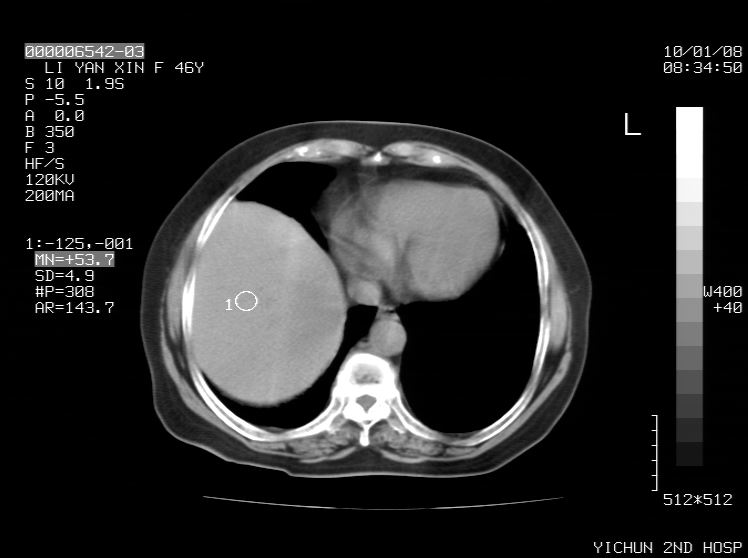

右侧膈膨升,胆囊壁厚,右侧肾脏缺如。病史?

右侧膈膨升,肝内钙化灶,胆囊壁厚,右侧肾脏缺如。病史?

右膈膨出,肝脏变异,肝内钙化,右肾缺如,脾大。

右侧膈膨升,肝内胆管结石?

肝脏变异致膈升高,肝左叶肝内胆管结石.右肾萎缩,左肾代偿肥大.

右侧膈膨升,肝内钙化灶,胆囊壁厚,右肾萎缩或发育不良。